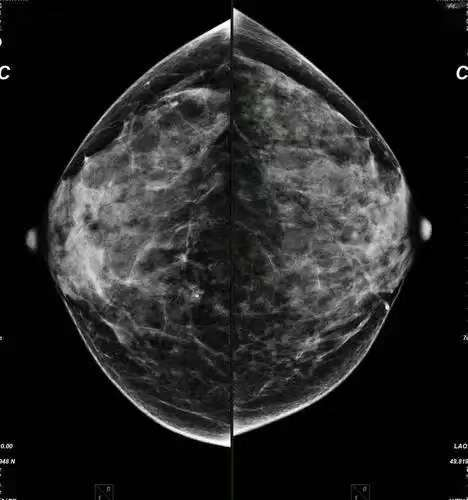

一、什么是乳腺X线摄影?

乳腺X线摄影是一种利用低剂量X射线对乳腺组织进行成像的医学影像学检查方法。它利用特殊的X光机拍摄出乳房的影像,医生通过这些影像观察乳腺结构是否正常,是否存在肿块或其他病变。

二、乳腺钼靶摄影有哪些特点?

1. 早期发现:乳腺X线摄影能够检测出体格检查触摸不到的乳腺肿块,特别是对于大乳房和脂肪型乳房。它还能观察到小于0.1毫米的微小钙化点,对乳腺癌的诊断敏感性和特异性都很高。

2. 无创性检查:乳腺X线摄影相对无创,简便易行,且分辨率高,重复性好,留取的图像可供前后对比。